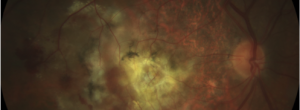

Update on Geographic Atrophy in Age-Related Macular Degeneration.

Intra and interobserver agreement in the classification of fundus autofluorescence patterns in geographic atrophy secondary to age-related macular degeneration.